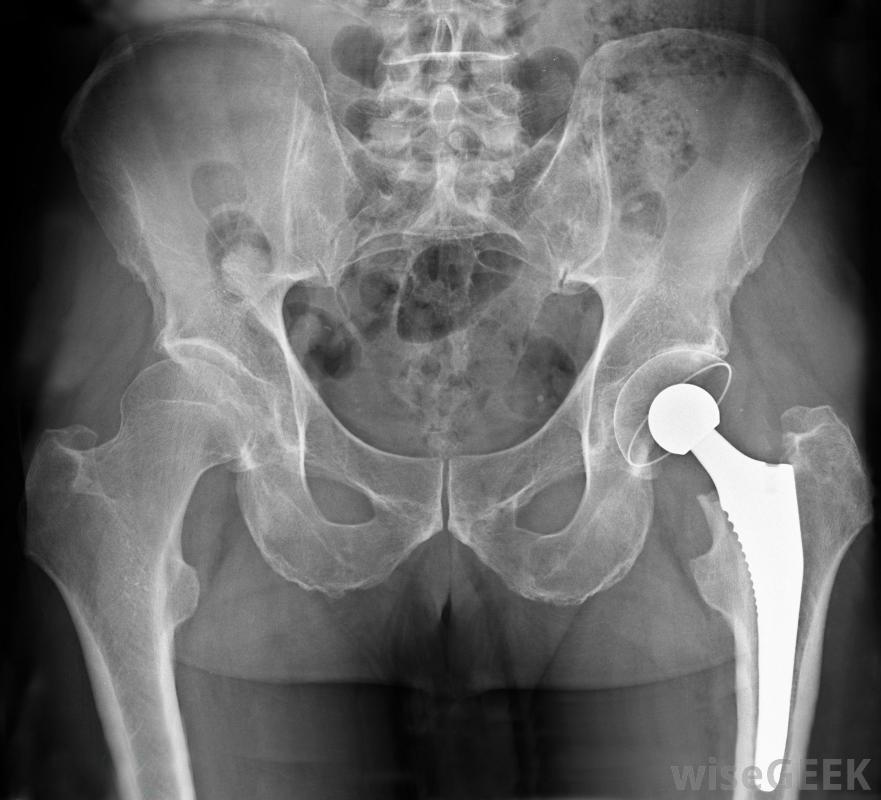

在髋关节置换手术中,股骨顶部是用假肢代替股骨骨折通常发生在骨头的颈部。在年轻人中,骨折通常是由于严重的跌倒、打击、运动损伤,或者交通事故。老年人的病因可能是骨质疏松症,骨质疏松症会加速骨质疏松症。老年人有时也会在颈部略低于股骨粗隆间的区域发生股骨骨折。无论是年轻人还是老年人,股骨骨折通常都会发生通常被认为是严重损伤的髋部骨折。骨折的愈合需要三到六个月。